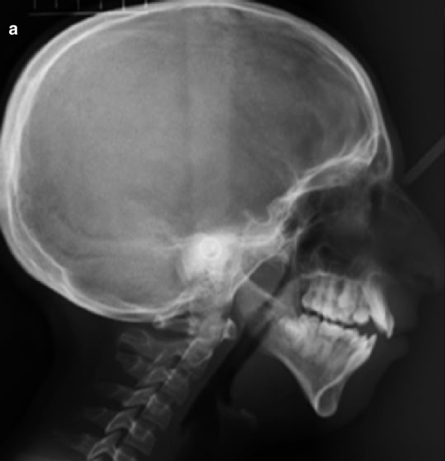

When I first started doing research about the jaws, I came across the information that physiologically, the maxilla grows downward and forward, as depicted in these pictures:

But that is wrong. It does not grow in this manner; it never did and never will. This is the point at which every single doctor, researcher, historian, or scientist makes a mistake. This is the first step in the evaluation of the skull’s shape and if you make the mistake here, you are guaranteed to fail in the steps that come next...